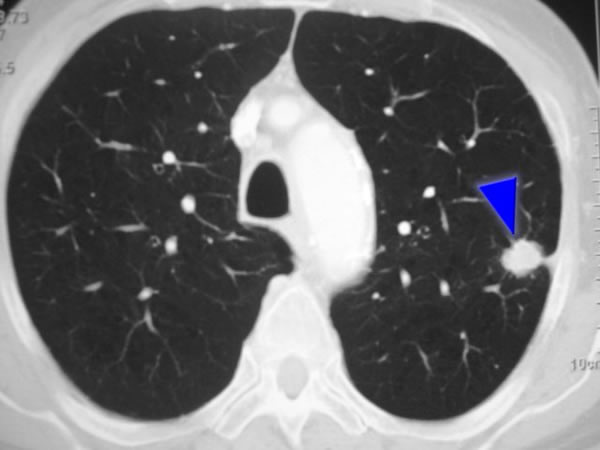

La precisión diagnóstica de la broncoscopia con navegación no fue inferior a la de la biopsia transtorácica con aguja en pacientes con nódulos pulmonares periféricos de 10 a 30 mm. Se presentó neumotórax en el 3,3% de los pacientes del grupo de broncoscopia con navegación y en el 28,3% del grupo de biopsia transtorácica con aguja. New England Journal of Medicine, 18 de mayo de 2025.